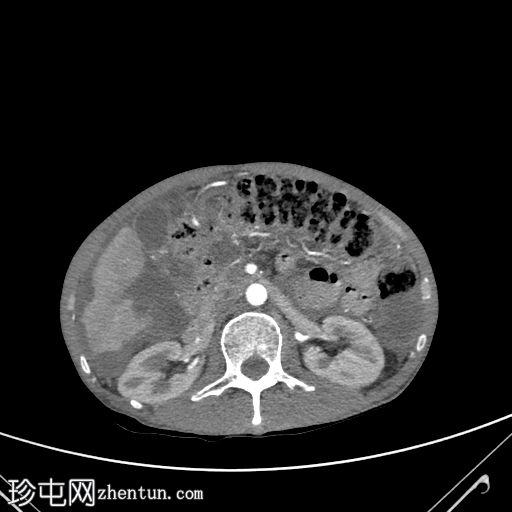

轴位口服增强扫描

大网膜和肠系膜内可见低密度、不均匀的腹膜积液,脏器表面呈扇形凹陷,尤其以肝脏和脾脏最为明显。

直肠穹窿可见一处厚度 1.2 cm、长 4.0 cm 的增强壁增厚。可见病灶周围及骶前淋巴结肿大,最大者直径 1.6 cm。

左下腹可见末端结肠造口。